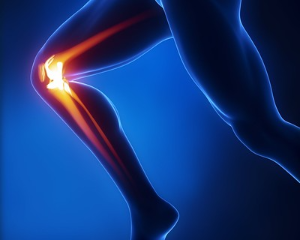

3. 콘드로이친 1200mg 효능 골관절염 진행 완화

게다가, 콘드로이친은 관절염의 진행을 늦추는 것으로 발표되었습니다. 관절염의 특징으로, 연골의 퇴화는 시간이 지남에 따라 관절 손상과 악화로 이어지게 되는데 연구에 따르면 콘드로이친은 연골을 보호하고 보존하는 데 도움을 줄 수 있으며, 잠재적으로 퇴행 과정을 늦추고 관절 건강을 유지할 수 있습니다.